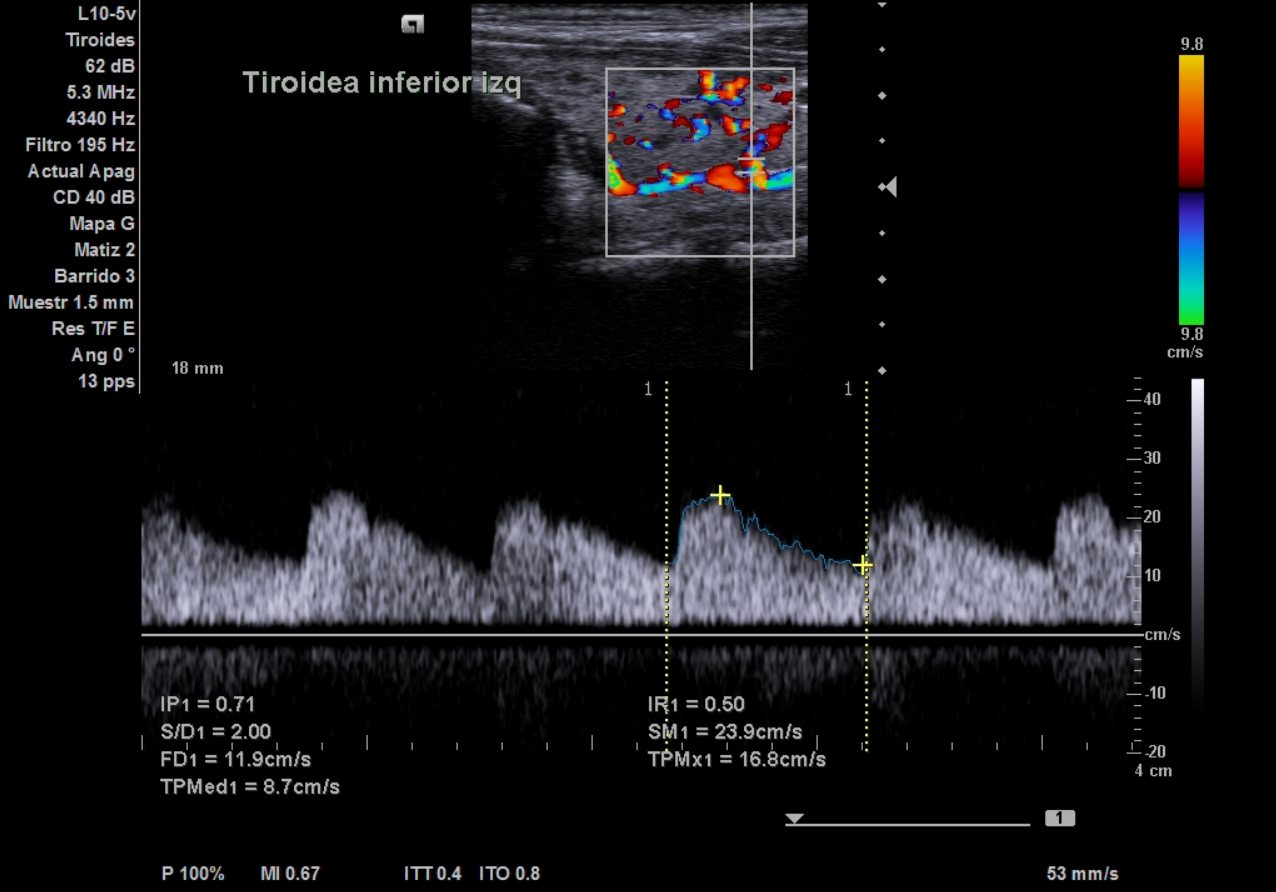

La ecografía clínica de tiroides muestra lóbulo derecho de 18 mm y lóbulo izquierdo de 16,7 mm en eje anteroposterior, con ecoestructura hipoecoica y heterogénea, presencia de múltiples quistes anecoicos milimétricos y un discreto aumento de la vascularización. No se identifican nódulos sólidos. El Doppler registra un pico sistólico máximo de 23 cm/s en ambas arterias tiroideas inferiores. Estos hallazgos son compatibles con tiroiditis.

Ecográficamente, la enfermedad de Graves se caracteriza por hipervascularización difusa («inferno tiroideo») y velocidades sistólicas elevadas (>30 cm/s), mientras que en las tiroiditis la vascularización es normal o discretamente aumentada, con patrón heterogéneo sin hiperflujo marcado.